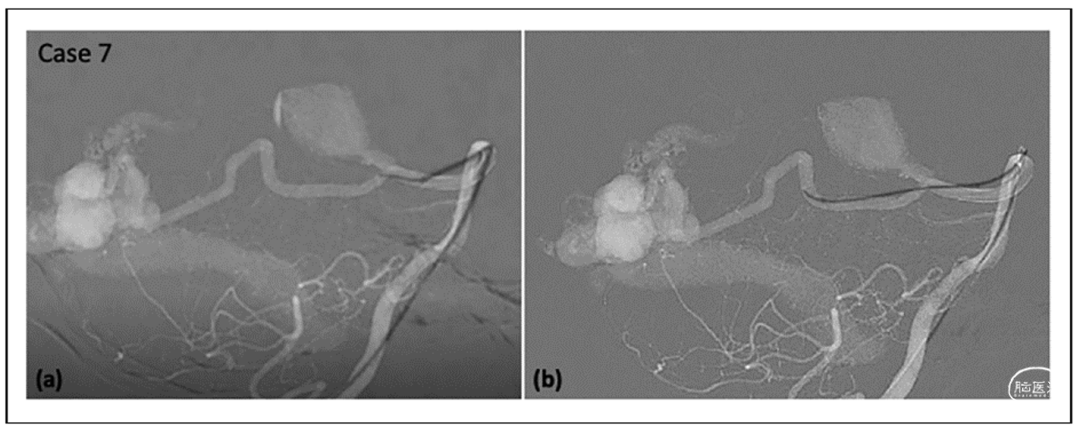

结果

病例集锦